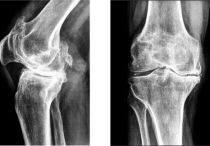

Боль внутри сустава может быть разной: сильной, слабой, ноющей или жгучей, но всегда она доставляет массу дискомфорта. Болевой синдром не дает человеку нормально двигаться, заниматься спортом, работать и даже отдыхать. Мучительные ощущения пронизывают сочленения насквозь.

Боли в суставах могут быть спровоцированы разными причинами: нарушением обменных процессов в организме и сочленении; неправильном кровообращении внутри мягких тканей, что не позволяет нормально питать хрящ. Кроме того, появлению боли способствуют инфекционные, системные, воспалительные, ревматические, эндокринные заболевания. Вызываются неприятные ощущения тем, что раздражитель активно воздействует на нервные окончания, которые тянутся от синовиальной сумки.

Какой бы ни была причина появления дискомфорта в суставе, повседневная жизнь больного значительно ухудшается. Часто человек может даже потерять свою трудоспособность и стать инвалидом.

Чтобы этого не допустить, необходимо обязательно лечиться. Но самостоятельно это делать не следует. Консультация грамотного специалиста – залог эффективности терапии. Если болят суставы, то это может говорить о развитии серьезной патологии в организме. Шутить с таким состоянием нельзя.